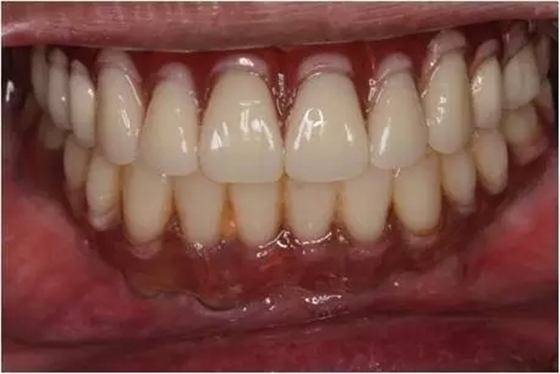

患者男性,51歲,全口無(wú)牙,下頜骨量尚可,上頜后牙區(qū)上頜竇底剩余骨高度嚴(yán)重不足,前牙區(qū)牙槽突較豐滿,主訴希望全口種植固定義齒修復(fù)。于2015年 9月接受種植治療:上頜采用All-on-4種植方案、下頜采用常規(guī)種植6顆種植體方案,種植后行即刻修復(fù)(圖1-2)。

10個(gè)月后出現(xiàn)左上頜咬合痛,X線檢查發(fā)現(xiàn)上頜左側(cè)前磨牙區(qū)傾斜種植體周圍低密度影,臨床檢查種植體松動(dòng),其余種植體骨結(jié)合良好,遂拔除該種植體(圖3-4)。愈合3個(gè)月,CBCT片顯示:25區(qū)種植窩空虛(圖5),愈合不佳,26區(qū)竇底剩余骨高度不足2mm(圖6),其余種植體骨愈合良好,15區(qū)傾斜種植體邊緣骨疑似吸收至第三螺紋(結(jié)合全景片)?;颊咭蠊潭ㄐ迯?fù)。